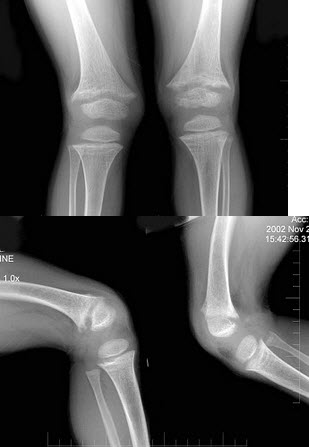

182、单项选择题

男,8岁。跌倒时手掌着地,查体:肘部明显肿胀,有压痛,肘关节呈半屈曲状向外突出畸形,肘后三角尚存。

首先应做进行的肘部辅助检查为()

258、单项选择题

男,7岁,肘部外伤,根据所示图像,最可能的诊断是()

A.尺骨中上段骨折